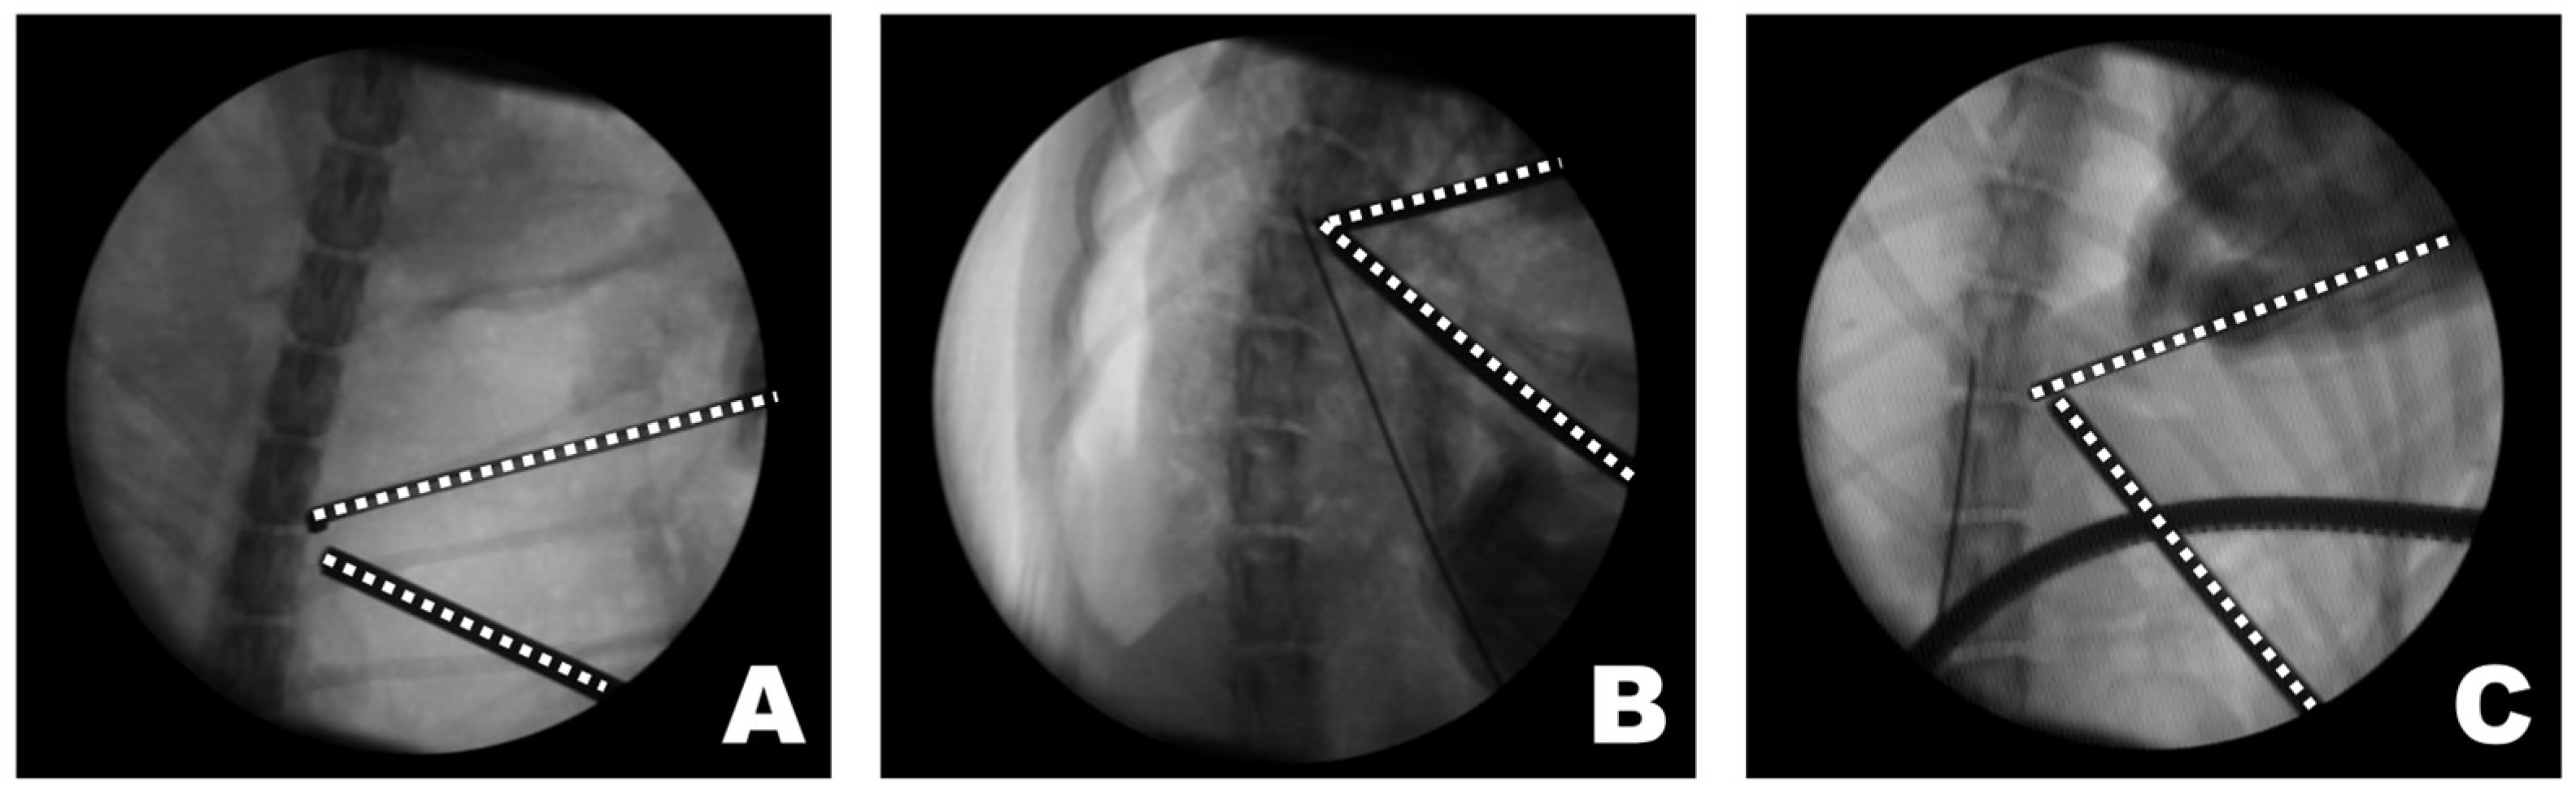

The triangular portal arrangement influenced working space formation and endoscopic visualization (Figure 8). When an appropriate triangular configuration was achieved, a working space was created at the target point, and the tip of the instrument remained consistently visible. In this configuration, instrument manipulation and visualization could be maintained simultaneously within the endoscopic field. In the open triangular configuration, a working space was not formed, and the instruments were not visible. This configuration was associated with failure to establish a functional working corridor at the target point. Although the working space was formed in a closed triangular configuration, it was located away from the target point, and only the shaft of the instrument, rather than the tip, was observed. As a result, precise manipulation at the accessory process was limited despite the presence of a working space.

Figure 8.

Observations of the triangular formation of the endoscope and working instrument from the dorsoventral view of the fluoroscopy. (A) In an open triangle formation, a working space was not created, and the instruments were not visible. (B) In a perfect triangle formation, the working space was appropriately created at the target point, and the visualization of the instrument’s tip was accurate. (C) In a close triangle formation, while a working space was formed, it was not at the target point, and the shaft of the instrument, rather than its tip, was observed. The dashed lines indicate the tips of the endoscope and the working instrument.

Maintaining an accurate triangular portal configuration is a fundamental technical requirement of BESS to preserve a stable endoscopic field and efficient irrigation flow [47,62]. In BESS, irrigation fluid introduced through the scope portal drains naturally toward the working portal without suction, making precise triangular alignment critical for maintaining a clear and directional fluid flow. Inadequate portal convergence may compromise visualization and working space formation, potentially prolonging the surgical time and increasing soft tissue manipulation [47,63,64]. Specifically, an open triangular configuration may prevent the formation of an effective working space at the target point, whereas premature convergence of the portals can result in a working space formed away from the accessory process, limiting visualization of the instrument tip. These technical considerations underscore the importance of precise portal planning and intraoperative spatial awareness in veterinary BESS.